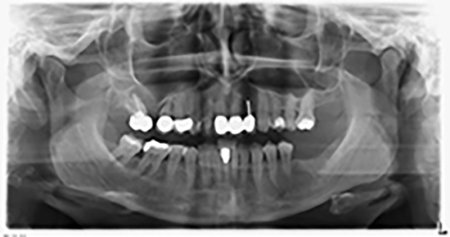

The 59-year-old patient presented with an advanced case of periodontitis, describing an unpleasant feeling and poor taste from the first quadrant in a distal direction. The clinical examination revealed generally enlarged periodontal pockets and very advanced bone atrophy in regions 16 and 14. The radiology confirmed the findings (Fig. 1). Teeth 16 and 14 could not be retained.

Image 1: Orthopantomogram with bone atrophy in region 16–14. *

About six months after teeth 16 and 14 were extracted, a digital volume tomography (DVT, Planmeca) examination was performed for planning and risk minimization purposes. It clearly showed that the bone had not regenerated to the desired volume (Fig. 2 to 7).

Image 2 to 7: DVT with greatly reduced horizontal bone volume.

A sinus floor elevation was required in both regions 16 and 14 to guarantee a fixed restoration based on at least two implants. Relatively large-scale bone augmentation was required due to the residual bone volume being extremely low in this case. Major bone augmentation procedures are invasive and linked to higher patient morbidity, as well as being time-consuming and expensive. It is more difficult to predict the results of the treatment and the risk of failure is increased. The patient was informed of the increased risk and was offered a removable solution, which she consistently rejected.

To restrict the augmentation to region 14, and in consultation with the patient, it was planned that implant 16 would be placed, inclined, in the dorso-cranial direction (Fig. 8).